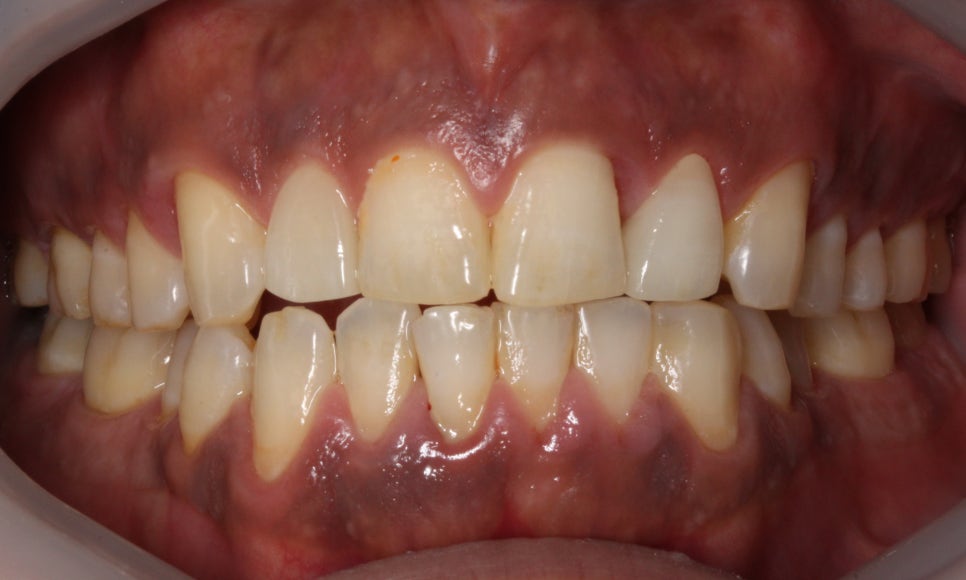

□ 앞니 노화

출처:투디 치과/앞니 노화 사례의 블링스 전후 사진입니다.

앞니 노화의 전, 후 사례입니다.

앞니가 노화되고 치아도 마모된 전 사진은

블링스를 만나고 자연스럽게 개선된 모습입니다!